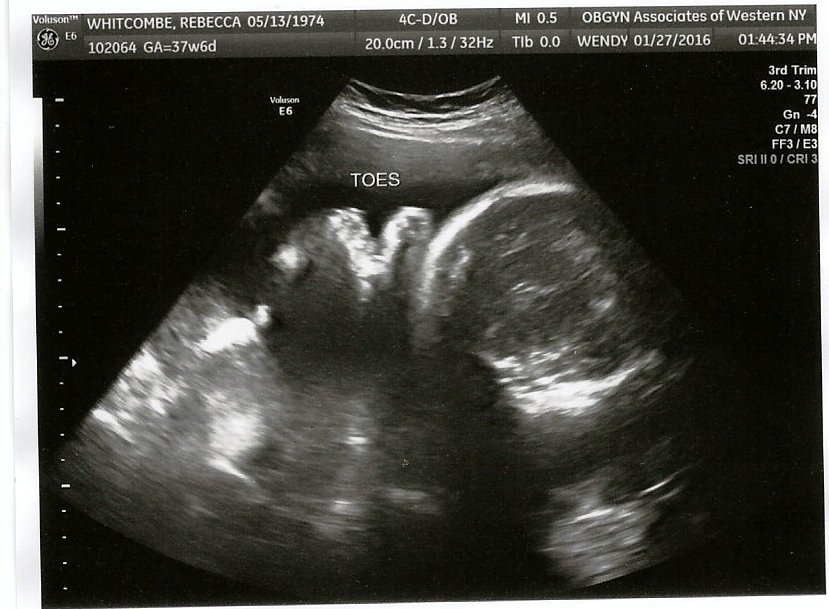

Final Day, Final Sonogram

Well little guy its almost show time. Final visit to the OB/GYN for the last scan.  You wiggled through most of and then curled up in a ball so no good pics of you today, just fingers and toes. Tomorrow we will get to meet you.  Your estimated weight is 5lbs 11 oz....we will see how accurate our sonogram tech was.  They have gotten to know us very well at the doctors office.